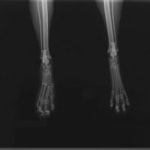

症例3:キルシュナーワイヤーのピンニングによる整復

ペルシャ猫 11ヶ月齢 雄

他院にて左大腿骨遠位の成長板骨折(salter-harrisⅠ型)が認められており、治療相談を目的として来院。当院にて、キルシュナーワイヤーを用いたピンニングにより骨折部位の整復を行いました。術後の経過は良好で、現在も経過観察中です。

術前レントゲン

術後レントゲン